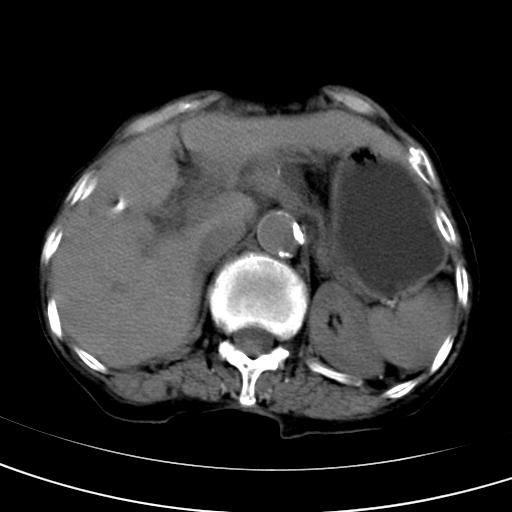

以下是引用wolft在2008-3-5 12:30:00的发言:[br]肝脏未见明显肿块影,但肝左叶增大,跨越腹中线到达脾胃前,且有一血管过去,考虑为先天变异:獭尾肝,胆囊为慢性胆囊炎急发,但胰腺头颈部有增大,密度不均匀,应该ct增强一下。

以下是引用zjzjr在2008-3-5 16:41:00的发言:[br]1.考虑慢性胰腺炎急性发作,建议增强除外占位性病变.[br]2.胆囊结石伴胆囊炎.[br]3.肝内胆管结石.